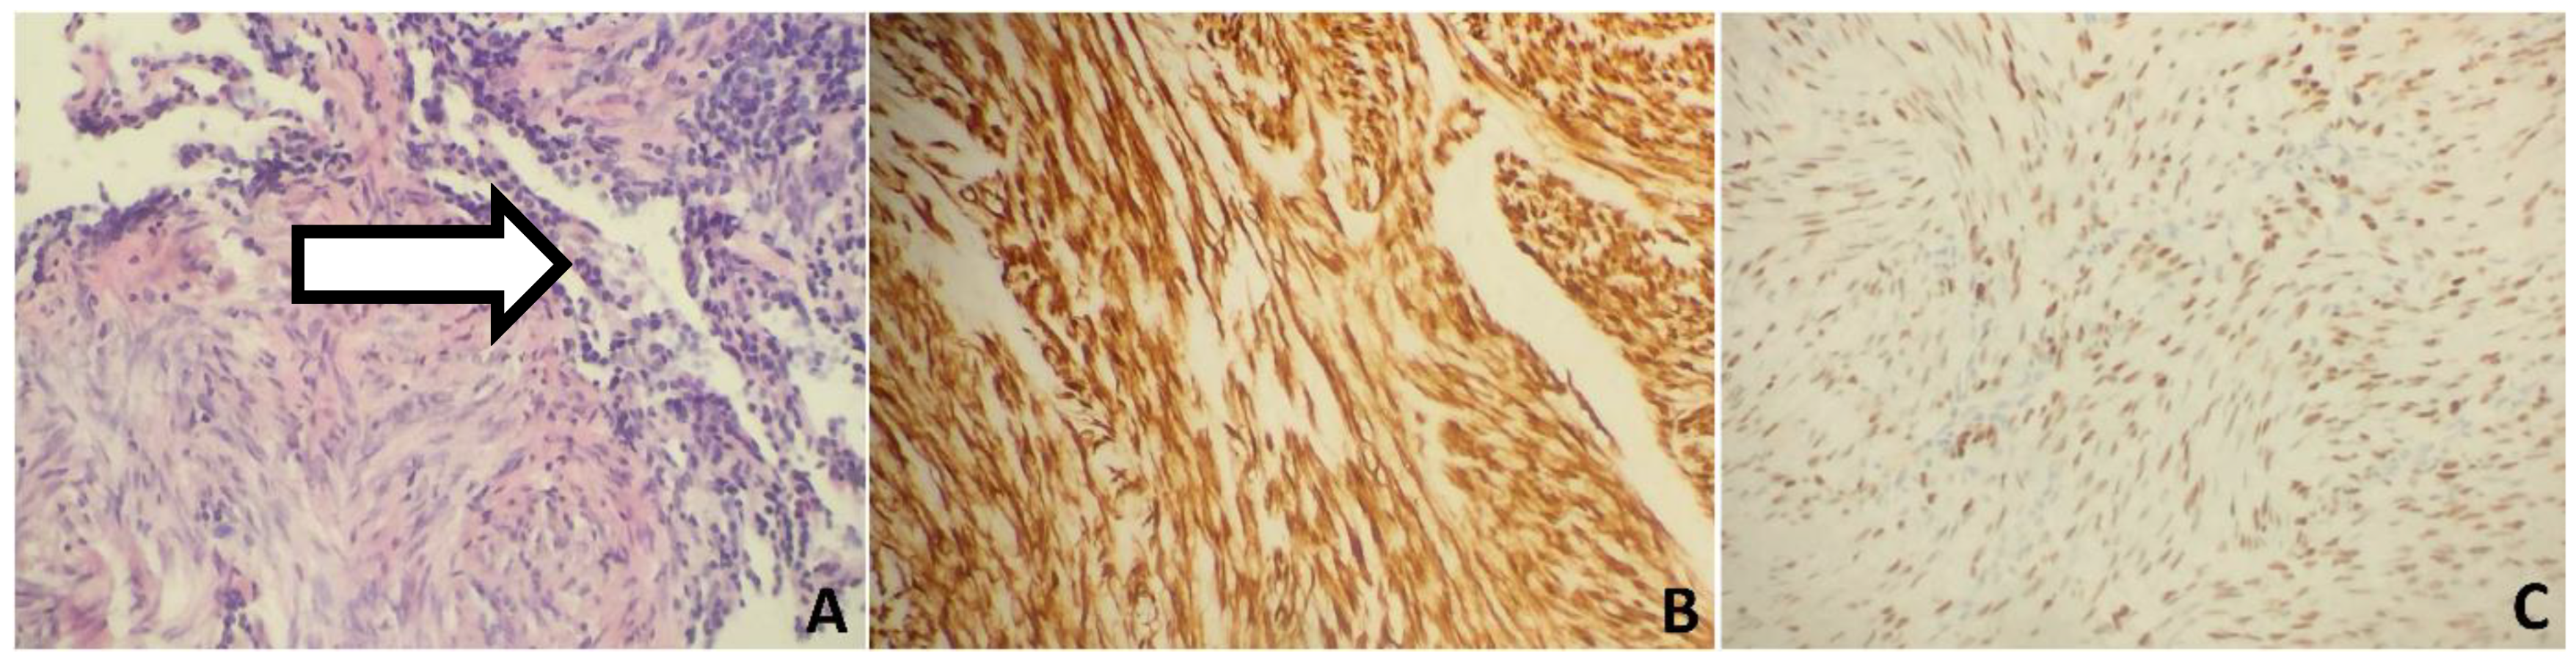

2. Case 1